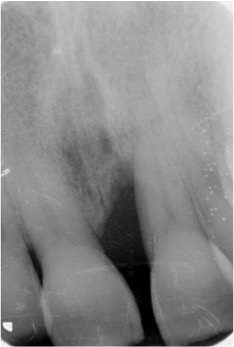

Fotos dos casos clínicos